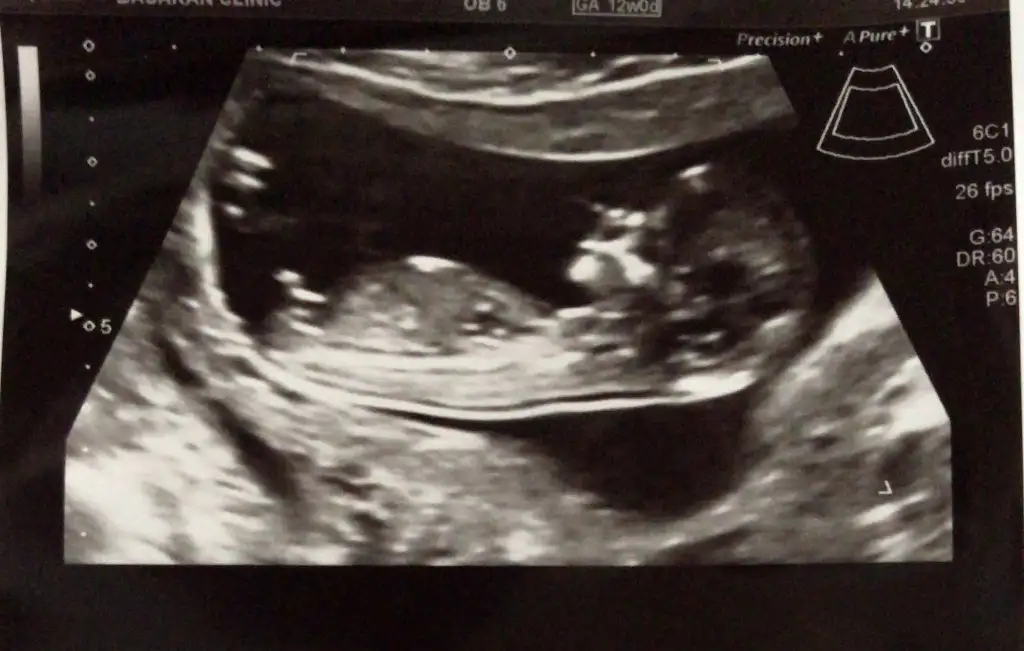

Bugün 12.hafta kontrolüne gittim ikili tarama için doktor cinsiyetine %75 erkek gibi dedi tabi yanılma payı vardır yoktur bilemicem başta sağlıklı olmasını diliyorum rabbimden:)

Ben şimdilik tahmininizin kısmen tuttuğunu söylemek için yazdım özellikle.. ultrason fotosunu da ekliyim 12.hafta içinde nub teoremiyle tahminlerinizi alıyım böylece birlikte teyit etmiş olalım şimdiden teşekkür ediyorum :)

Aynen nubu dik erkek 😊 kesinleşince anketimi oylarsanız sevinirim 😊